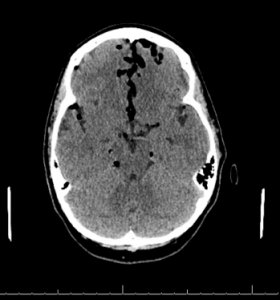

Figures 1 (ABOVE) and 2 (BELOW): CT scan with large-volume atraumatic pneumocephalus.